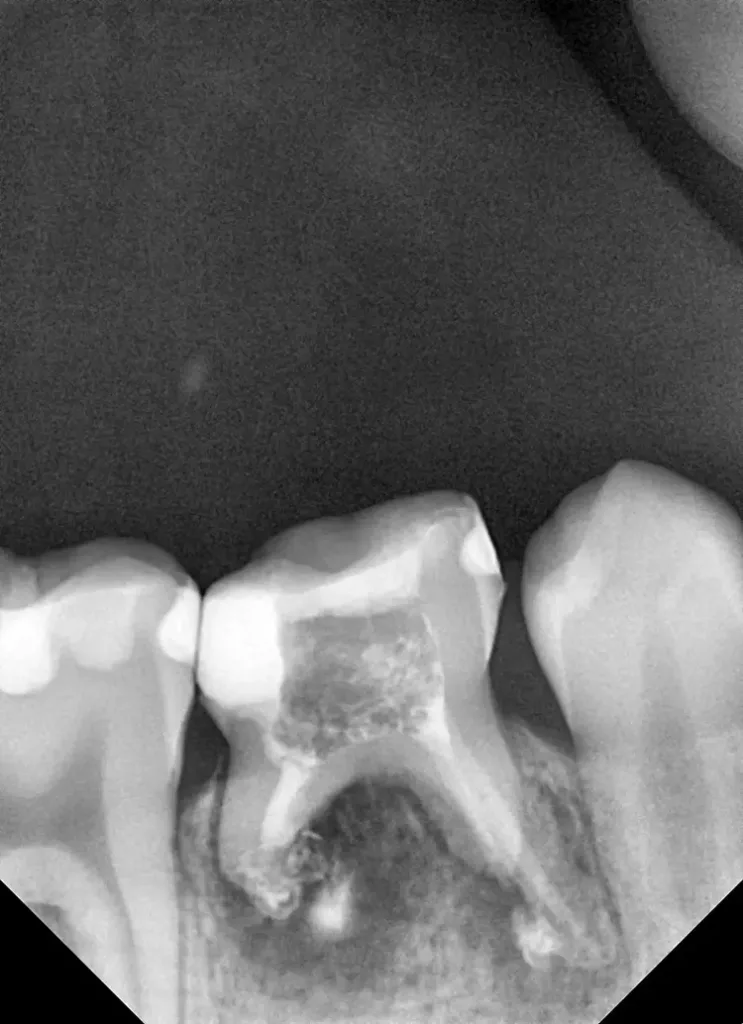

Auf einer die Untersuchung ergänzenden Röntgenaufnahme wurden die Nichtanlage des 2. Prämolaren und die Wurzelresorption mit einem periapikalen Prozess festgestellt (Abb. 1). Weil es keine Anzeichen einer Ankylose oder einer Infraokklusion gab, welche das Wachstum des Alveolarfortsatzes stören könnten, wurde nach eingehender Aufklärung über die Therapieoptionen und die Prognose gemeinsam mit den Eltern beschlossen, einen Behandlungsversuch zum Erhalt dieses Zahnes zu starten.